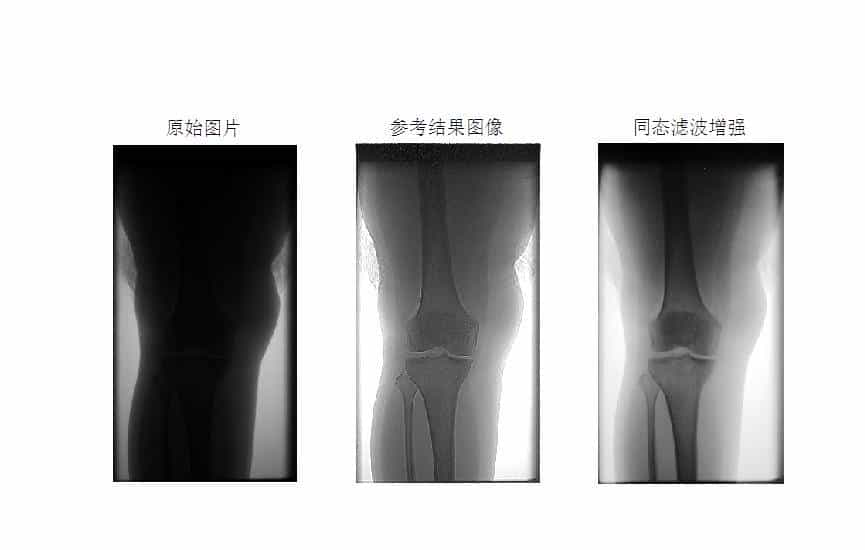

MATLAB环境下使用同态滤波方法进行医学图像增强

同态滤波是一种结合了频率过滤和灰度变换的方法,它以图像的照度反射模型作为频域的处理基础,分别对低频信息进行增强,高频信息进行抑制,可以有效解决图像上照度不均匀和 动态范围过大对图像产生影响的问题,在不损失亮区细节信息的同时,有效增强暗区的细节信息。

本文以医学图像为例,使用同态滤波方法进行医学图像增强。

结果如下: